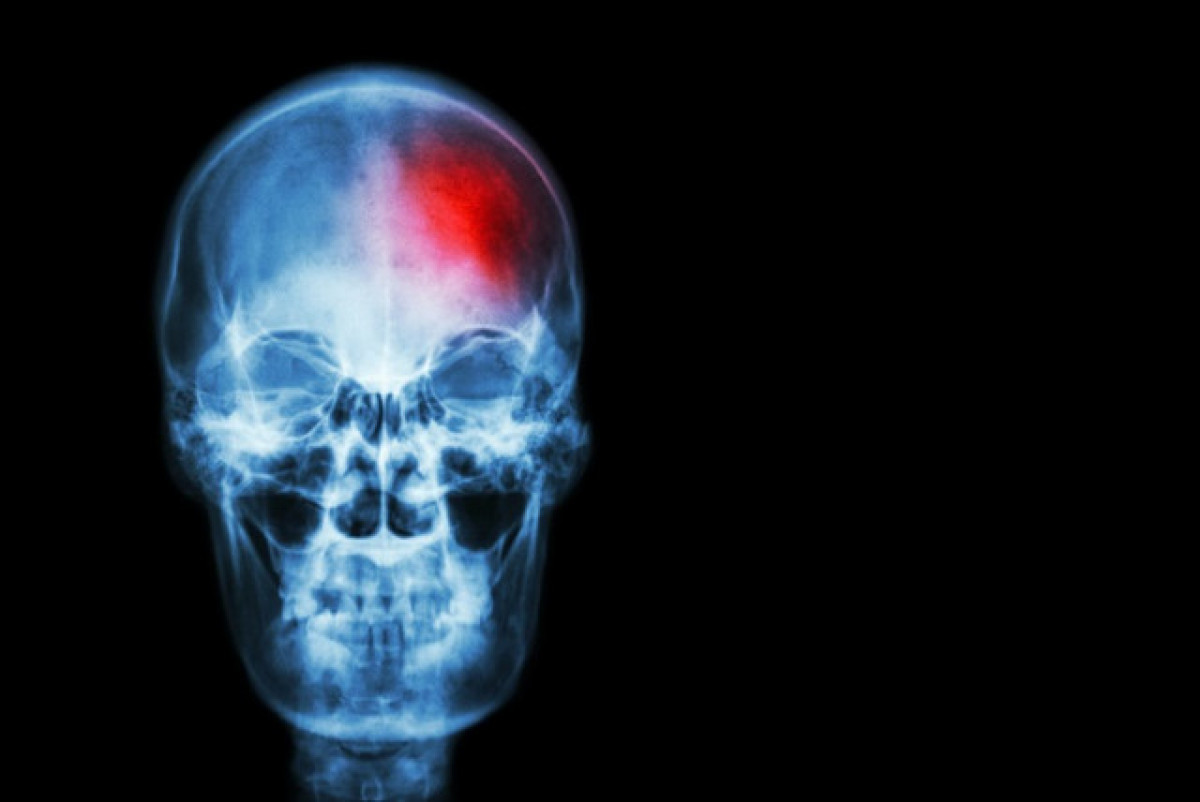

Ictus @ep

Els investigadors es van centrar principalment en els casos d' accident cerebrovascular isquèmic , que és el tipus més comú d'accident cerebrovascular. L'accident cerebrovascular isquèmic passa quan un coàgul de sang bloqueja o estreta els vasos sanguinis que subministren sang al cervell. Els investigadors també van examinar alguns casos d'accident cerebrovascular causat per hemorràgia cerebral, que és un tipus d'accident cerebrovascular menys comú però força greu.